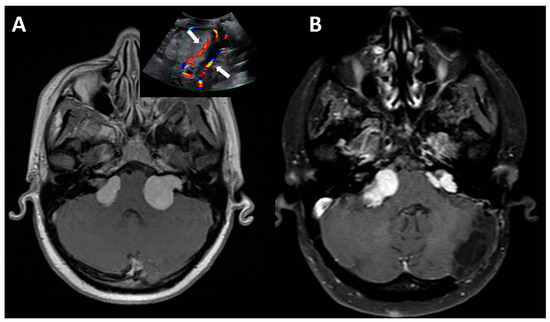

NF1 with Multiple Cardiac Structural Abnormalities Leading to Cerebral Infarction

Background/Objectives: Neurofibromatosis type 1 (NF1) is an autosomal dominant disorder driven by mutations in the NF1 gene, whose pathogenesis centers on the loss of neurofibromin function and subsequent hyperactivation of the RAS/MAPK pathway. Notably, to the best of our knowledge and following [...] Read more.

Background/Objectives: Neurofibromatosis type 1 (NF1) is an autosomal dominant disorder driven by mutations in the NF1 gene, whose pathogenesis centers on the loss of neurofibromin function and subsequent hyperactivation of the RAS/MAPK pathway. Notably, to the best of our knowledge and following a systematic literature search conducted by our research team, no cases of NF1 complicated by severe cardiac structural abnormalities that ultimately lead to cerebral infarction have been reported to date. Thus, it is of paramount importance to avoid missed diagnosis by performing comprehensive cardiac-related examinations in patients with NF1. Case Presentation: A 20-year-old male patient diagnosed with NF1 presented with right-sided limb weakness and was initially identified with cerebral infarction. To clarify the underlying etiology, a comprehensive clinical evaluation was performed, including cardiac imaging assessments (to characterize cardiac structural changes) and whole-exome sequencing (to identify the presence of procoagulant gene mutations). Comprehensive evaluation revealed a spectrum of cardiac structural abnormalities in the patient: aortic valve prolapse with severe regurgitation, non-infective vegetations on the aortic valve leaflets, mild-to-moderate mitral regurgitation, left ventricular hypertrophy and dilation, and left atrial dilation. Whole-exome sequencing detected exclusively a pathogenic variant in the NF1 gene, with no other pathogenic/likely pathogenic variants or thrombophilia-associated polymorphisms being found. Laboratory investigations ruled out infectious etiologies, supporting the notion that NF1-mediated cardiac structural and developmental anomalies are the primary driver of cardiac vegetation formation, given the absence of other identified contributing factors; embolization of one such vegetation ultimately led to both splenic and cerebral infarction. Conclusions: This case emphasizes the necessity of implementing early and proactive cardiac evaluations in patients with NF1. Additionally, for NF1 individuals—particularly those presenting with suggestive vascular or cardiac symptoms—a comprehensive multifactorial assessment of thrombotic risk is critical. Collectively, maintaining clinical vigilance for cardiac abnormalities in NF1 patients and avoiding diagnostic oversight is essential to reduce life-threatening risks. Full article

Figure 1